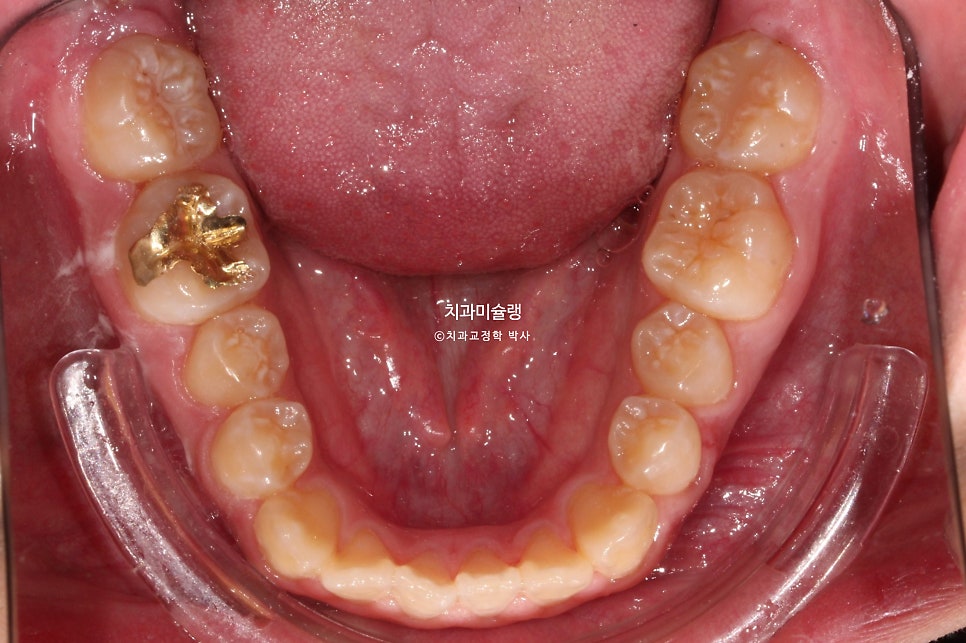

좌측 소구치 하나가 입천장으로 들어가 있는데 180도 회전된 상태입니다.